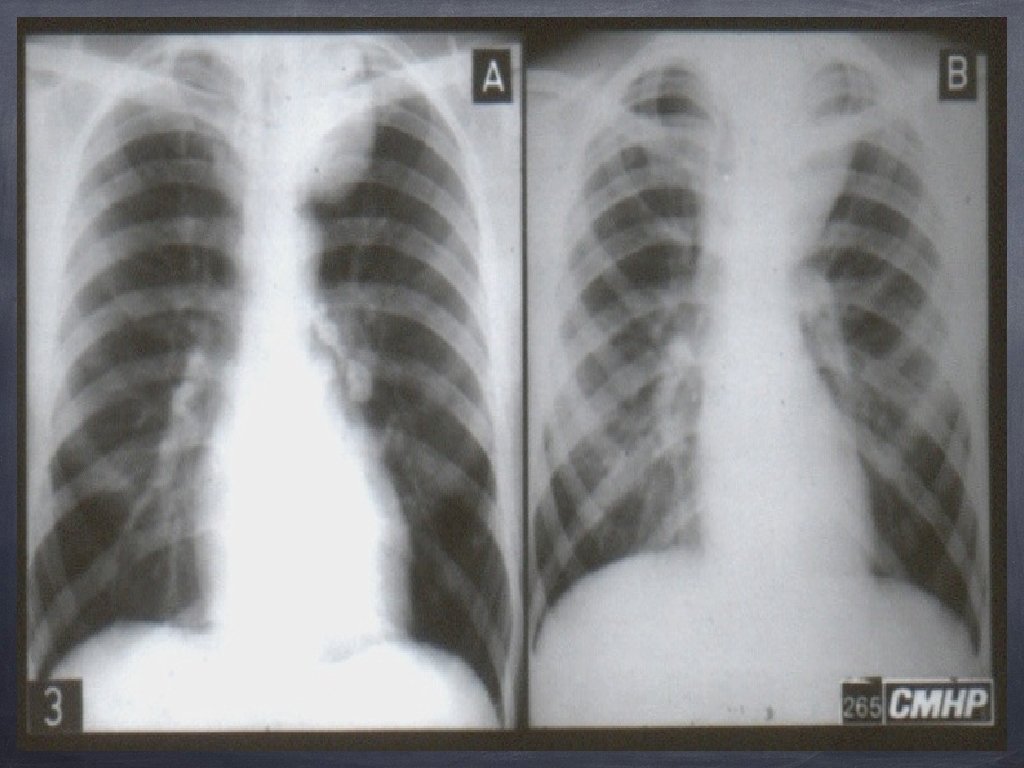

Semnul convergenței hilare